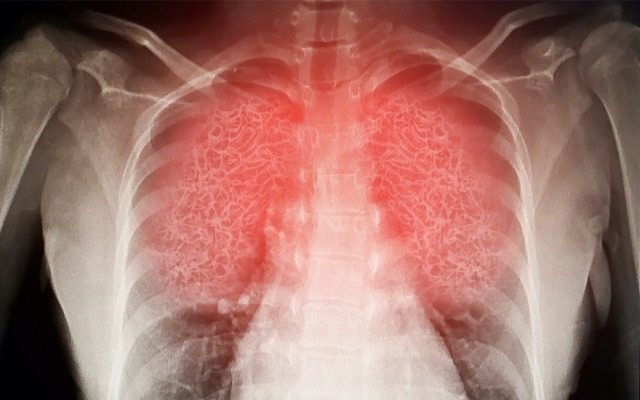

This can lead to “wet lung”, damaging the patient’s lung tissue and can ultimately lead to death, as has been seeing in some hospitalised COVID-19 patients.

SAARDS is characterised by widespread inflammation of the lungs (often referred to as ‘wet lung’ or pneumonia) inhibiting a patient’s ability to oxygenate blood.